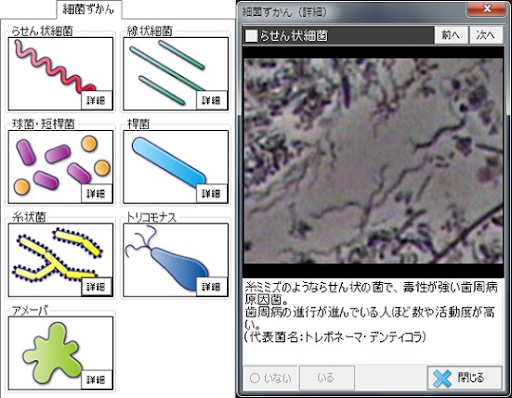

簡単に説明すると細菌には大小の違いがありますが、点状の球菌、棒状の桿菌、糸巻状のらせん菌、長く大きなひも状のカンジダ、虫のように動き回るアメーバやトリコモナス、赤血球や白血球、リンパ球、上皮が剥がれ落ちたものなどが観察され、それぞれの量や密度、活動状況が確認できます。

それでは、位相差顕微鏡で観察されるさまざまな菌について性質や特徴について解説いたしましょう。

らせん状の菌で、顕微鏡で容易に観察されやすい歯周病菌です。一番わかりやすく、この菌が多く存在して元気に活動しているようなら歯周病対策をしっかり行う有力な指標となります。

グラム陰性嫌気性菌で、運動性が高くらせん状をしており、スピロヘータ属にはいります。

免疫反応を制御して炎症の慢性化に関与する、たいへん厄介な細菌です。

難治性の歯周病患者で、歯肉から排膿しているところに必ず存在していて、人の腸管や泌尿・生殖器表面等全身から検出されます。